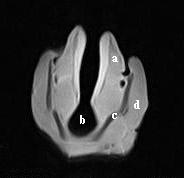

| dc.description.abstract | A study was performed to establish the appearance of normal equine laryngeal cartilages using magnetic resonance imaging. Specimens were acquired from clinically normal horses that were euthanized for reasons other than respiratory disease. Three in situ and 5 ex vivo larynges were imaged using a 0.3 Tesla system. Images were obtained in the transverse plane using T1-weighted 3D spin echo, T2-weighted 3D spin echo, T2-weighted gradient echo, short tau inversion recovery (STIR), and proton density spin echo sequences. Five ex vivo larynges were also imaged in the transverse plane using a 1.5 Tesla system, sequences included T1-weighted 3D spin echo, T2-weighted 3D turbo-spin echo, turbo inversion recovery (TIRM), and proton density spin echo sequences. A frozen gross laryngeal specimen was sliced in 5-mm transverse sections for comparison to the MR images. Excellent correlation was found between MR images and the gross transverse sections. Successful imaging was accomplished using both imaging systems; however, the 1.5 Tesla system yielded superior image resolution. The 0.3 Tesla imaging system would accommodate the intact equine head, which was not possible using the 1.5 Tesla MRI system. The internal morphology of the laryngeal cartilages was clearly identified in all imaging sequences obtained. Cartilages were found to differ in signal intensity based on the tissue composition and imaging sequences performed. MRI was determined to be a useful imaging modality for evaluating the cartilage morphology of the equine larynx. Further investigation is required to document pathologic morphology. | en |